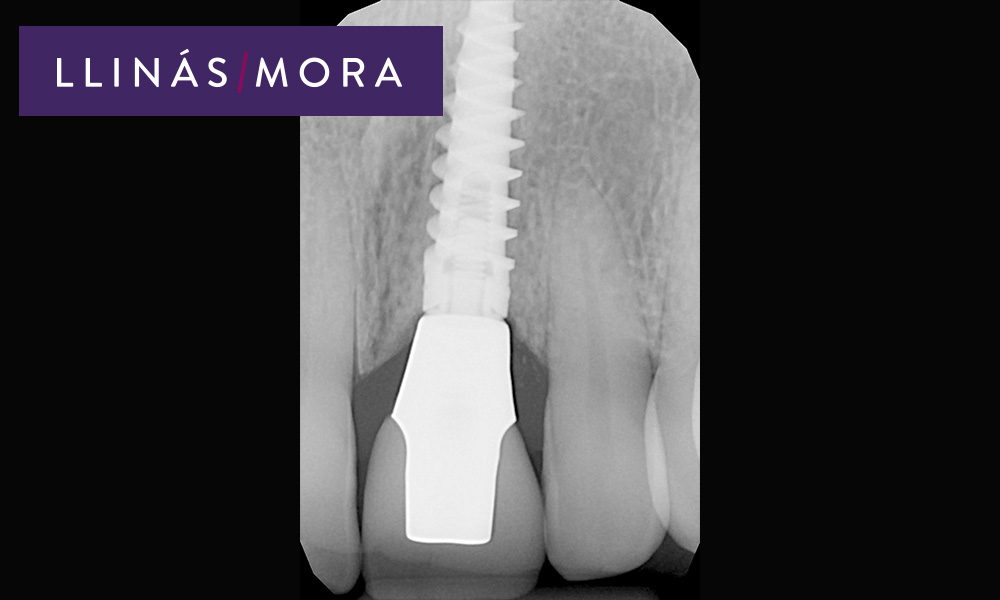

6. Pilar definitivo de zirconio a los 3 meses.

8. Radiografía del Implante